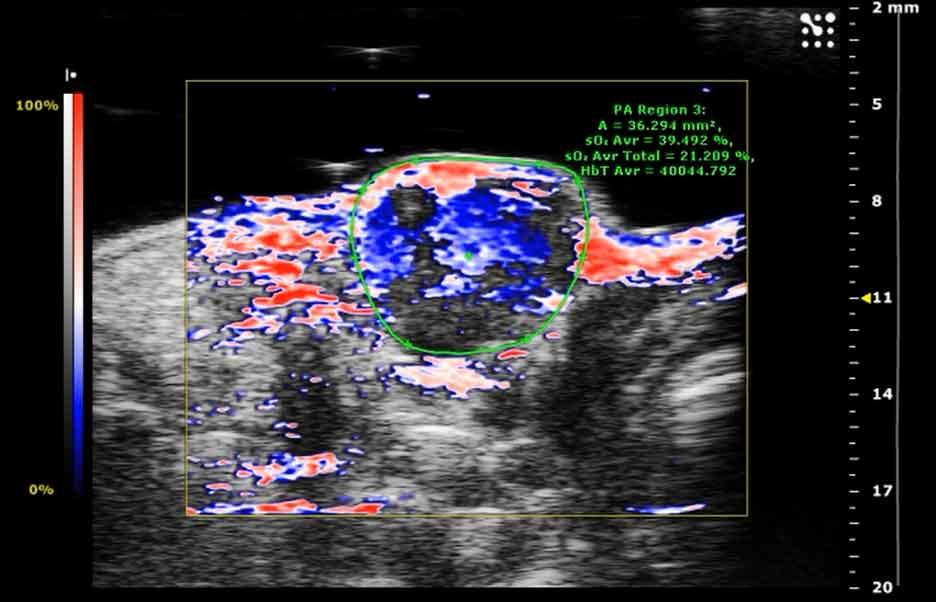

Photoacoustic ultrasound image displaying oxygen distribution (shown in red) within tumor tissue following microbubble delivery, with blue and white regions indicating other tissue characteristics and measurement data displayed on the screen.

Photoacoustic image showing oxygen (red) in tumor tissue after microbubble delivery.

Credit: John Eisenbrey, Ph.D., Thomas Jefferson University

The team then used both a mechanical probe and a type of imaging, called photoacoustic imaging, to measure oxygen in tumors before and after microbubble injection and ultrasound.

Using the probe, they found that on average, after the ultrasound pulse, oxygen in tumors increased to a level that would render cells sensitive to radiation, and these levels were maintained for at least 2 minutes.

Photoacoustic imaging showed that transportation of oxygen in the tumors did not rely on a molecule in the bloodstream called hemoglobin. The researchers were not expecting this, Dr. Eisenbrey said. But, he continued, the lack of dependence on hemoglobin transport may explain how the oxygen molecules also reached parts of the tumor not immediately adjacent to the blood vessels carrying the microbubbles.